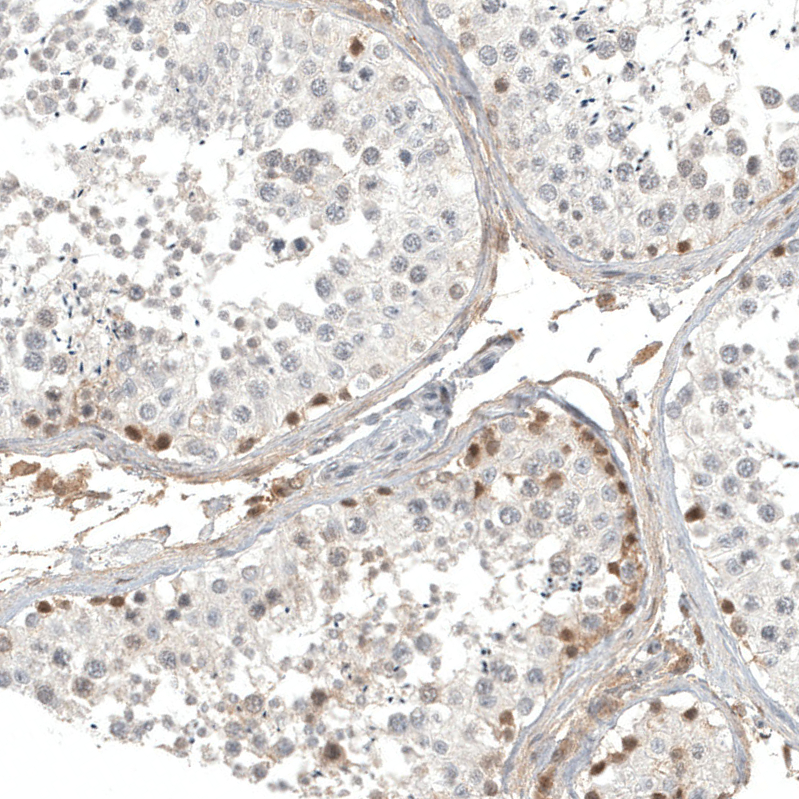

Immunohistochemistry analysis in human cerebral cortex and liver tissues using AMAb91814 antibody. Corresponding CALB2 RNA-seq data are presented for the same tissues.